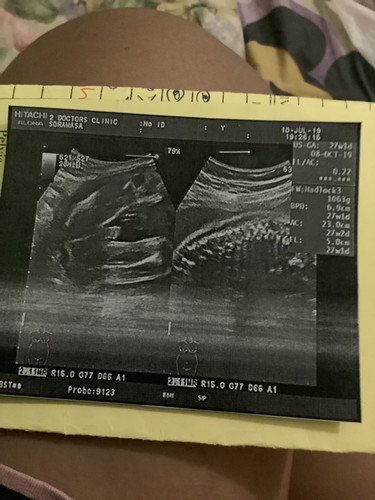

ผู้หญิงหรือผู้ชายค่ะ. อย่างรู้ให้แน่จัยยค่ะ

น่าจะชายนะค่ะ มีเจดีย์โผล่มา